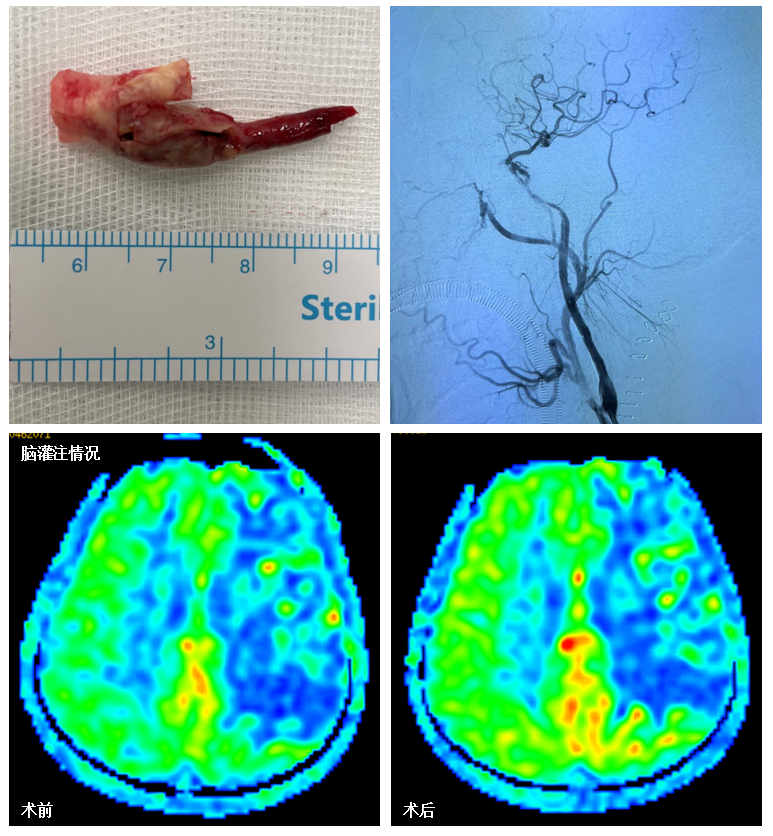

2022年6月10日,手术日。神经外科郭毅、范玉龙医师顺利完成左侧颈动脉内膜剥脱,在颈动脉切口处,由张小峰、苏伟、王也、徐文灯医师组成的介入团队,继续开通闭塞段。剩余闭塞段斑块又长又硬,给介入团队很大考验,最终通过抽吸取栓、球囊扩张、支架植入等多项技术的综合运用,颈动脉血流最终恢复通畅,颅内血管终于完整显影,呈现出正常血流频谱,正可谓应了那句“问渠那得清如许,为有源头活水来”。术中采用的脑血流监测技术、电生理脑电、脑氧监测等全方位多模态监护也为手术顺利保驾护航(图3)。血管再通成功,但远远不到可以庆祝的时候。术后,患者全麻状态下返回重症监护室,次日苏醒。在严格的动脉血压监测及管理下,患者未出现头痛、恶心、呕吐等脑过度灌注症状,亦未出现脑栓塞相关的新发症状体征。颈部手术切口顺利拆线,切口愈合良好。术前所担心的并发症都没有出现。更可喜的是,术后复查的头颅影像学发现左侧大脑半球灌注比术前有了改善(图4)!

图4:神经外科医师完成颈动脉内膜剥脱,后介入团队继续开通剩余血管,复查造影颈内动脉血流恢复通畅,术后复查头颅影像学提示左侧大脑半球灌注比术前改善。